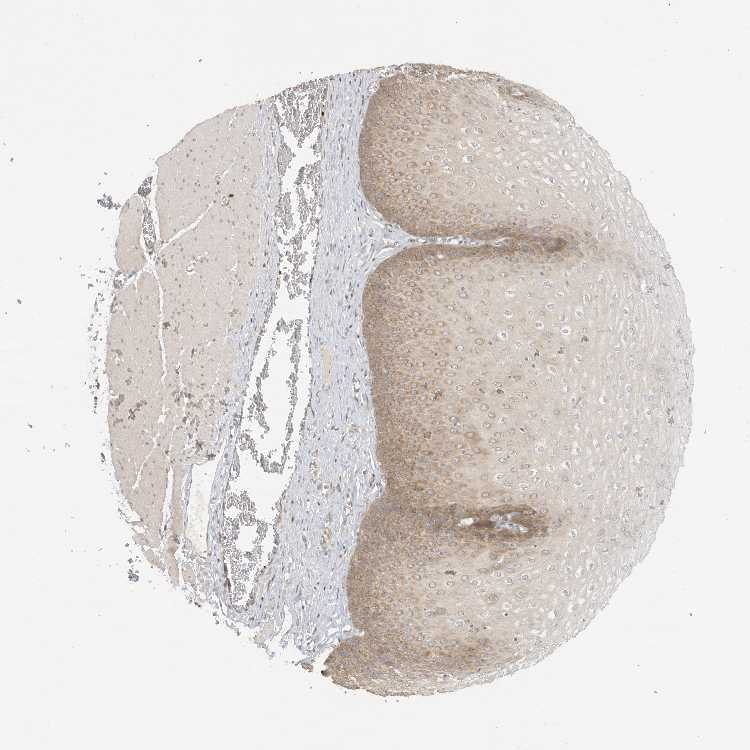

ESOPHAGUS - Antibody stainingi

Antibody staining in the annotated cell types in the current human tissue is reported as not detected, low, medium, or high, based on conventional immunohistochemistry profiling in selected tissues. This score is based on the combination of the staining intensity and fraction of stained cells.

Each image is clickable and will lead to virtual microscopy that enables deeper exploration of all samples and also displays staining intensity scores, fraction scores and subcellular localization as well as patient and tissue information for each sample.

Antibody HPA027424

Squamous epithelial cells Medium